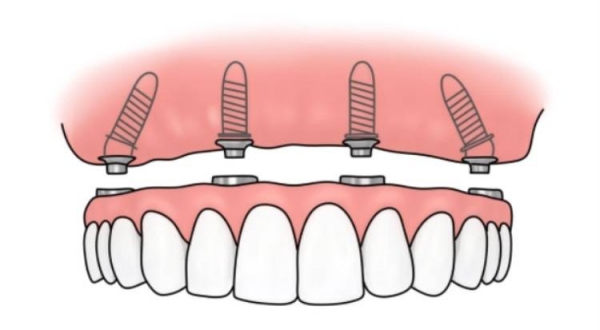

刘本义院长擅长各类种植牙项目,无论是常规单颗、多颗种植,还是高难度的all-on-4、穿颧穿翼种植,都能稳准完成,技术覆盖全场景缺牙修复需求。